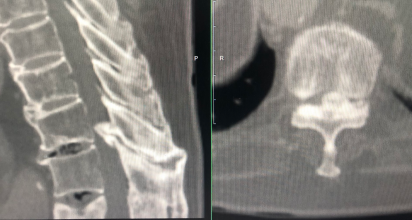

4、典型病例

昨日完成的一例胸椎黄韧带骨化症,椎管侵占率约80%,术中采用上述的分区椎板切除技术,完整切除骨化黄韧带和部分骨化硬膜,蛛网膜保持完整。